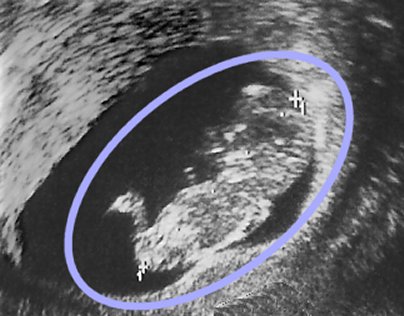

This sonogram, taken in the third month of pregnancy, shows a male fetus (head, body and legs are clearly recognizable inside the blue oval).